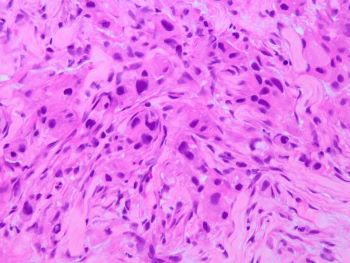

A 67-year-old male presents with a parotid mass associated with facial pain and cervical adenopathy. Fine-needle aspiration and core needle biopsy are performed and representative sections are shown.p63 immunostain is negative.

Brief explanation of the answer: The cytology smears show cells with oncocytic morphology and significant nuclear atypia. Histologic sections show pleomorphic tumor cells infiltrating as cords and nests. No keratinization or mucinous cells are noted. Salivary duct carcinoma is an important diagnostic consideration when encountering atypical oncocytic cells. This aggressive tumor typically affects older males and is associated with a poor prognosis. Tumor cells are positive for androgen receptor and GATA-3 and negative for myoepithelial markers. Some cases may also express Her2 by immunohistochemistry.